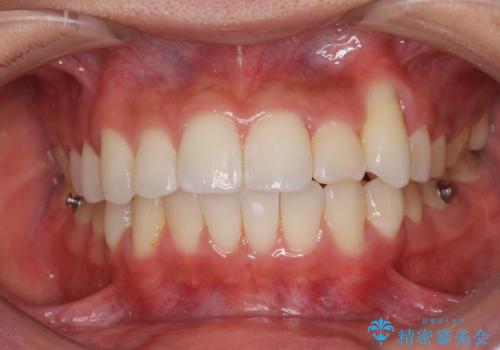

八重歯と奥歯のクロスバイト 上顎骨を拡大してインビザラインで矯正

- 八重歯を気にして来院された患者様です。

八重歯が著しいため、抜歯矯正も視野に入れて検討しましたが、臼歯の咬合関係は正常に近かったので、非抜歯矯正で進める方針としました。

上顎骨の幅が狭く、奥歯がクロスバイトとなっていたため、急速拡大装置を用いて上顎骨を側方拡大し、八重歯を収めるスペースを獲得しつつクロスバイトを改善することとしました。

上顎骨を思い通りに拡大できたため、当初の計画通りに非抜歯矯正で仕上げることができました。